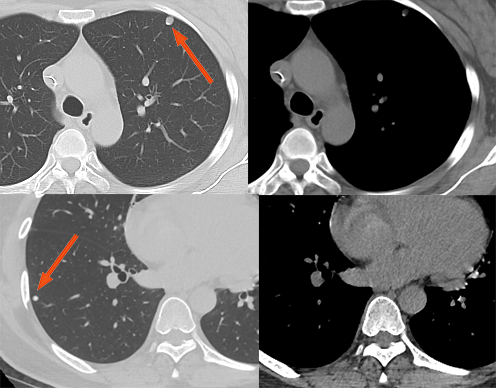

转移结节周围模糊影

有研究认为血管肉瘤和绒癌的肺转移最易发生出血,可能因为新生血管壁脆弱而易破裂,表现为结节周围磨玻璃样密度或边缘模糊的晕(晕征),而病灶周围片状影可能代表由于较大支气管黏膜下转移而导致的阻塞性炎症。

女性,52 岁。胰腺癌双肺多发转移,大部分转移结节周围可见磨玻璃密度晕征。

男,50 岁。肾透明细胞癌伴肉瘤样癌。双肺空洞型肺转移,部分周围可见「晕征」。双肺另有不伴有空洞的转移结节。